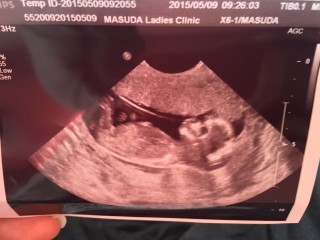

写真:13w6d:ぺこりんさん

今日から経腹エコーで、初めて3Dで動いている赤ちゃんを見ました!

おててを動かして、おしゃぶりしてるのかな?動きがとにかく可愛い!!

CRL83.8mmでまだまだ小さいのに、もうこんなに立派に赤ちゃんなんだと感動しました。

こんな可愛い赤ちゃんがお腹の中にいつもいるんだと思うと幸せでいっぱいです!!